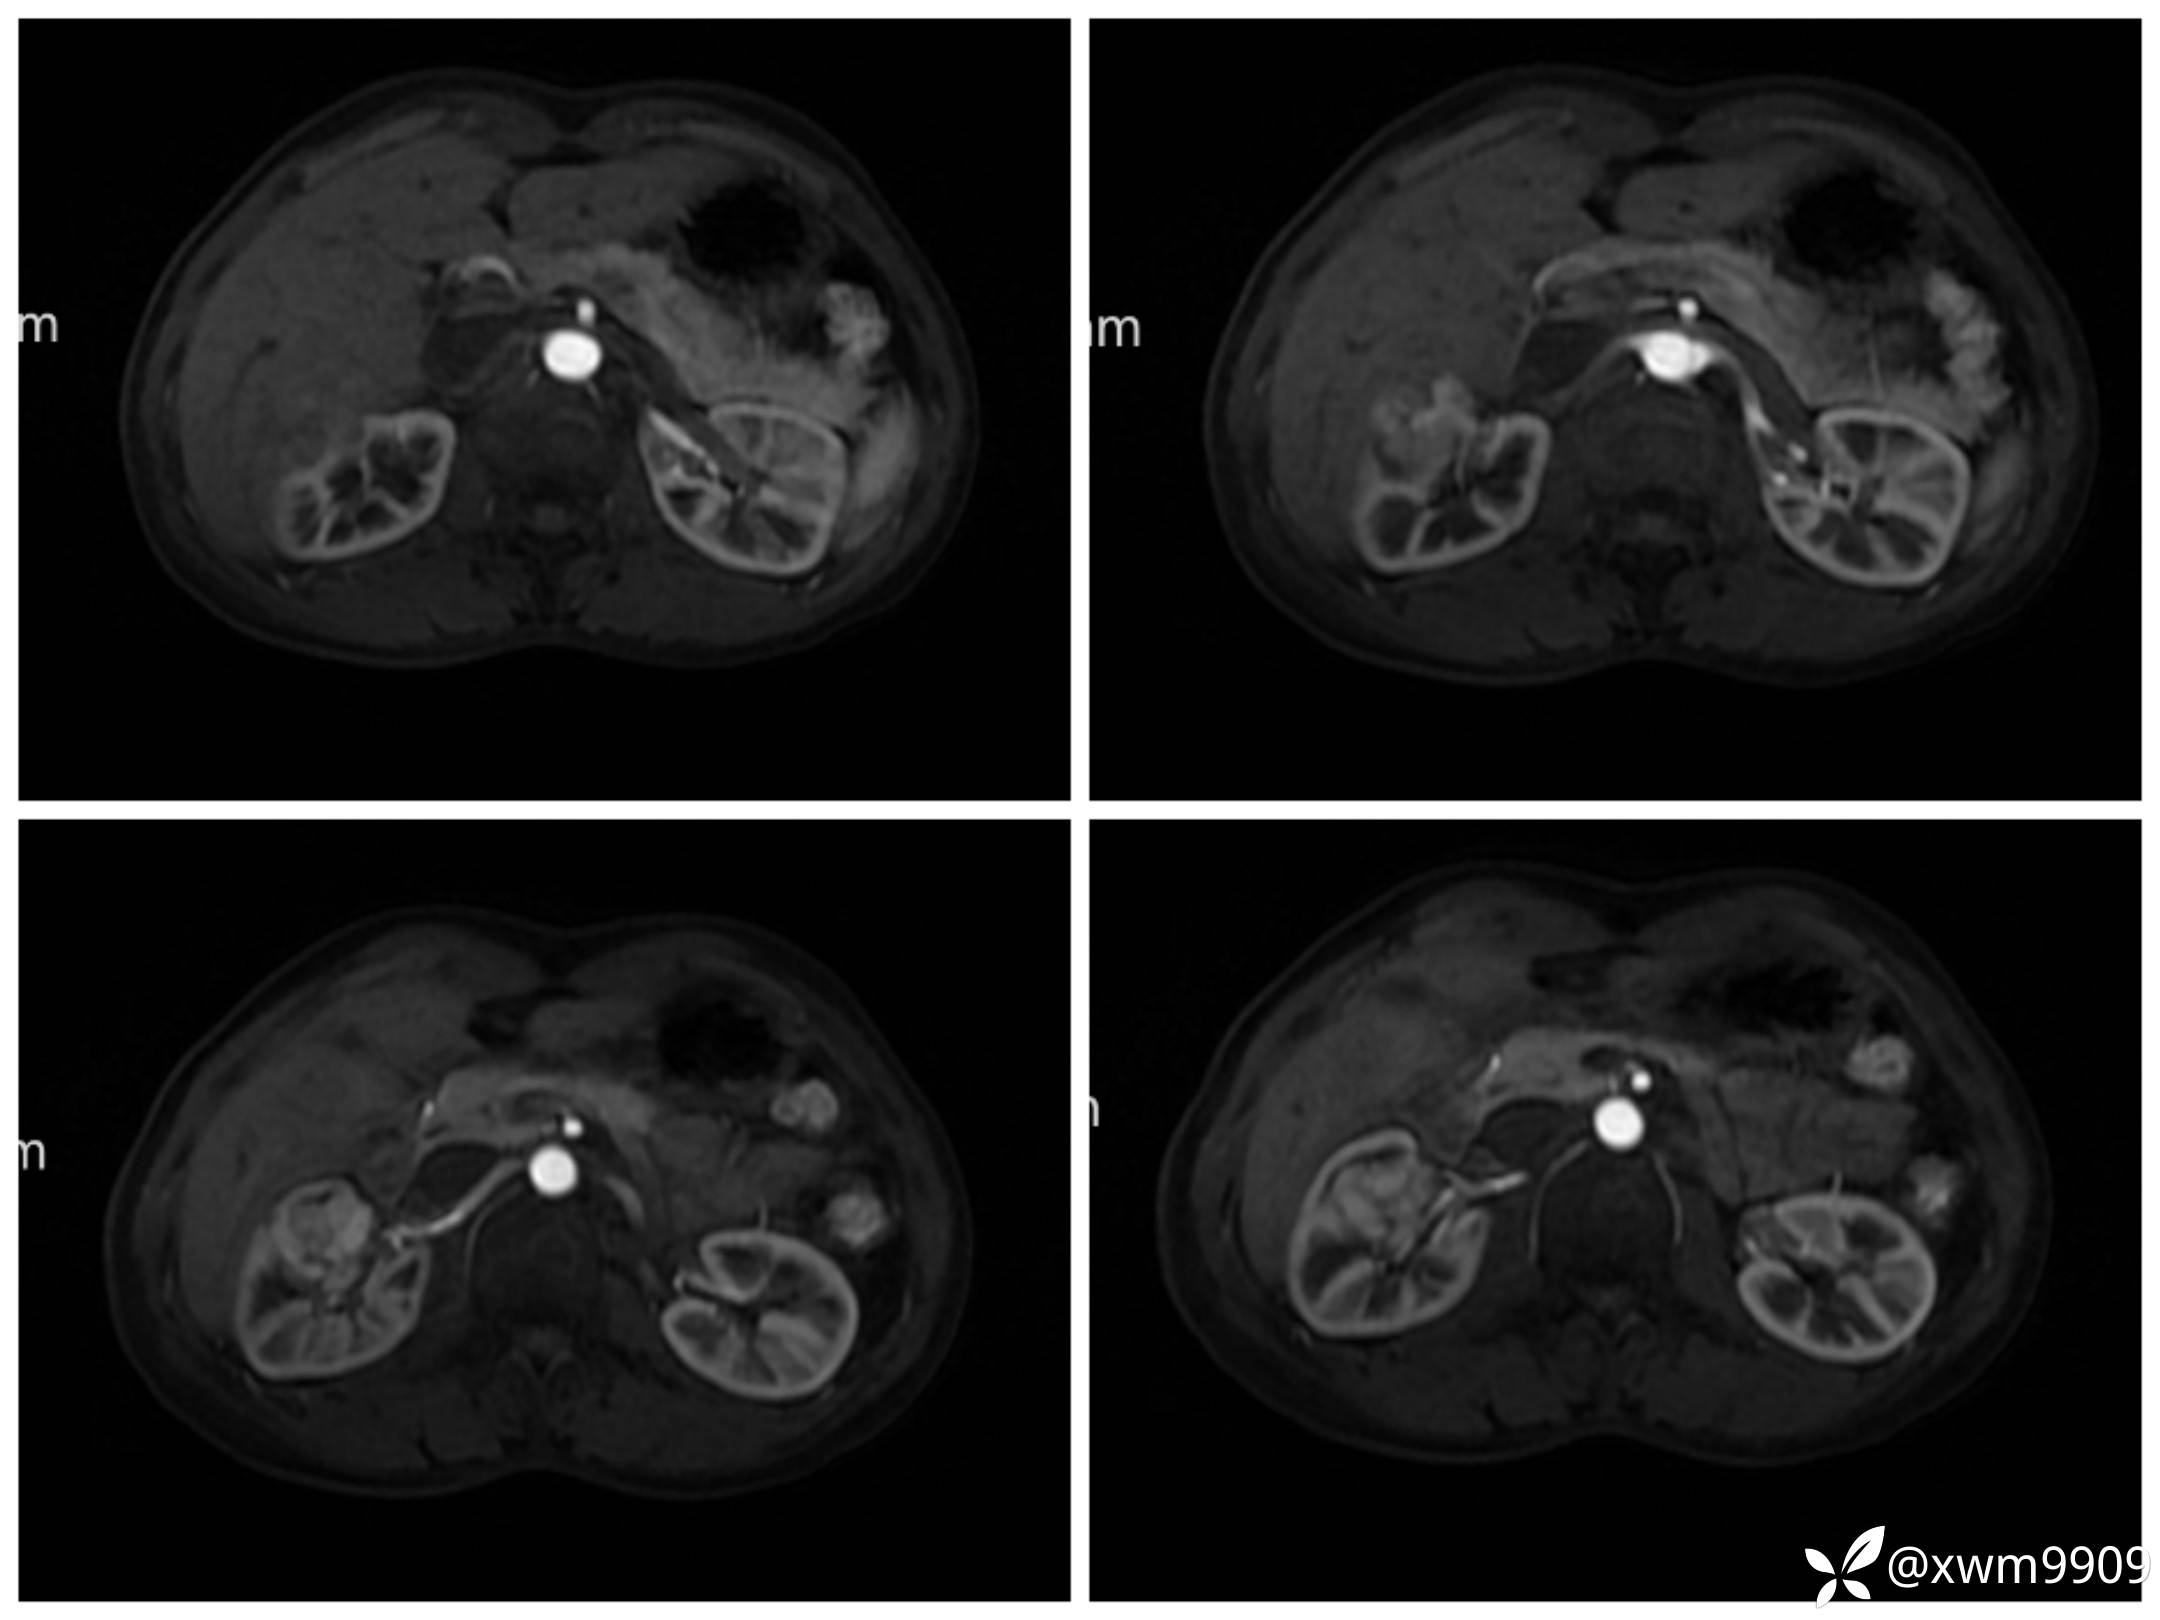

DwI丶ADC:

LAvA: